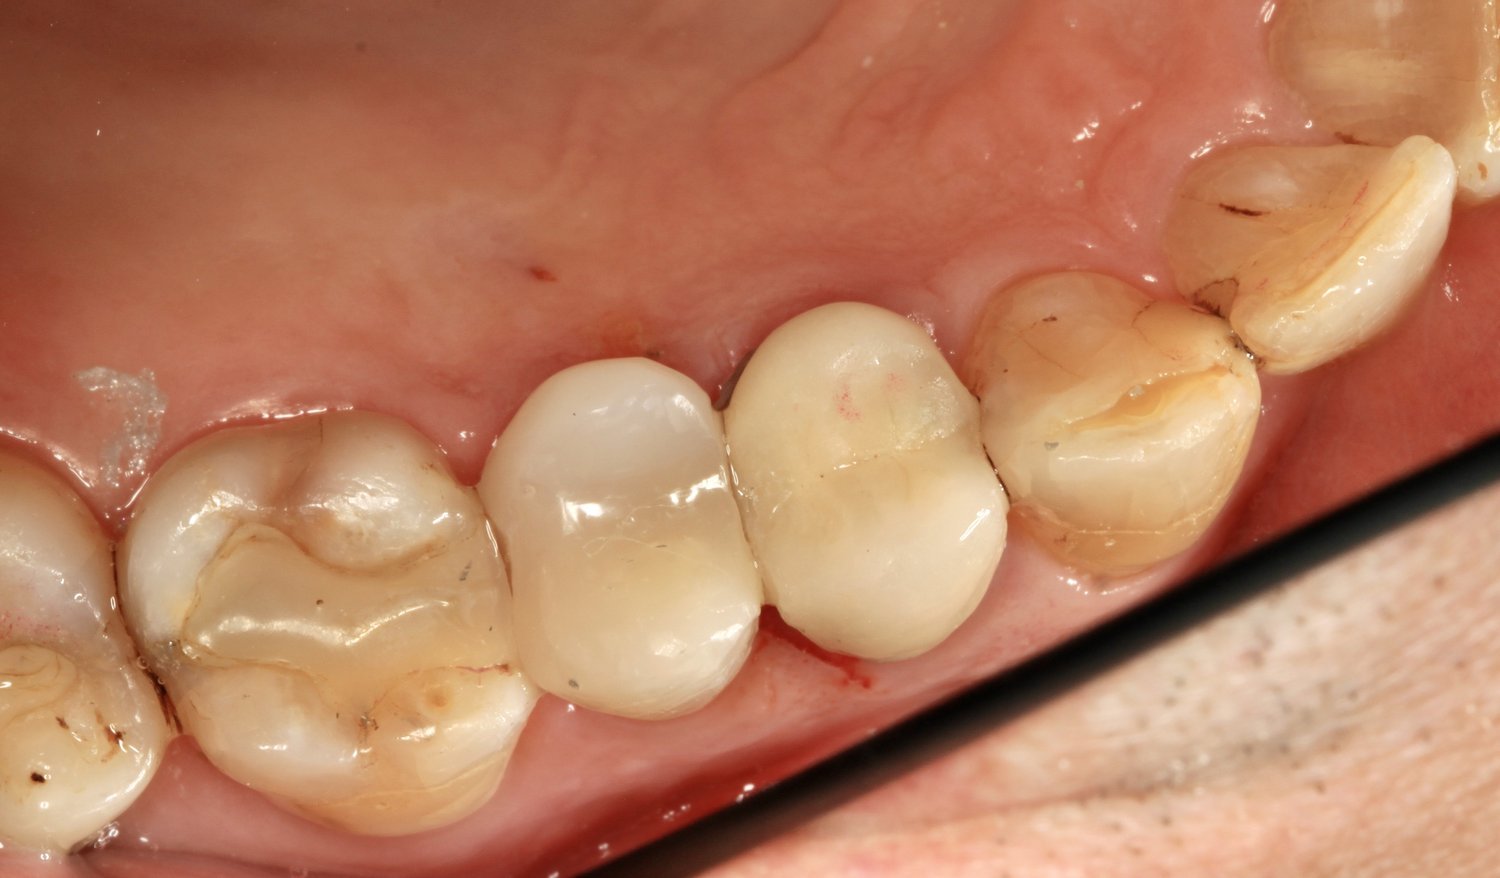

After